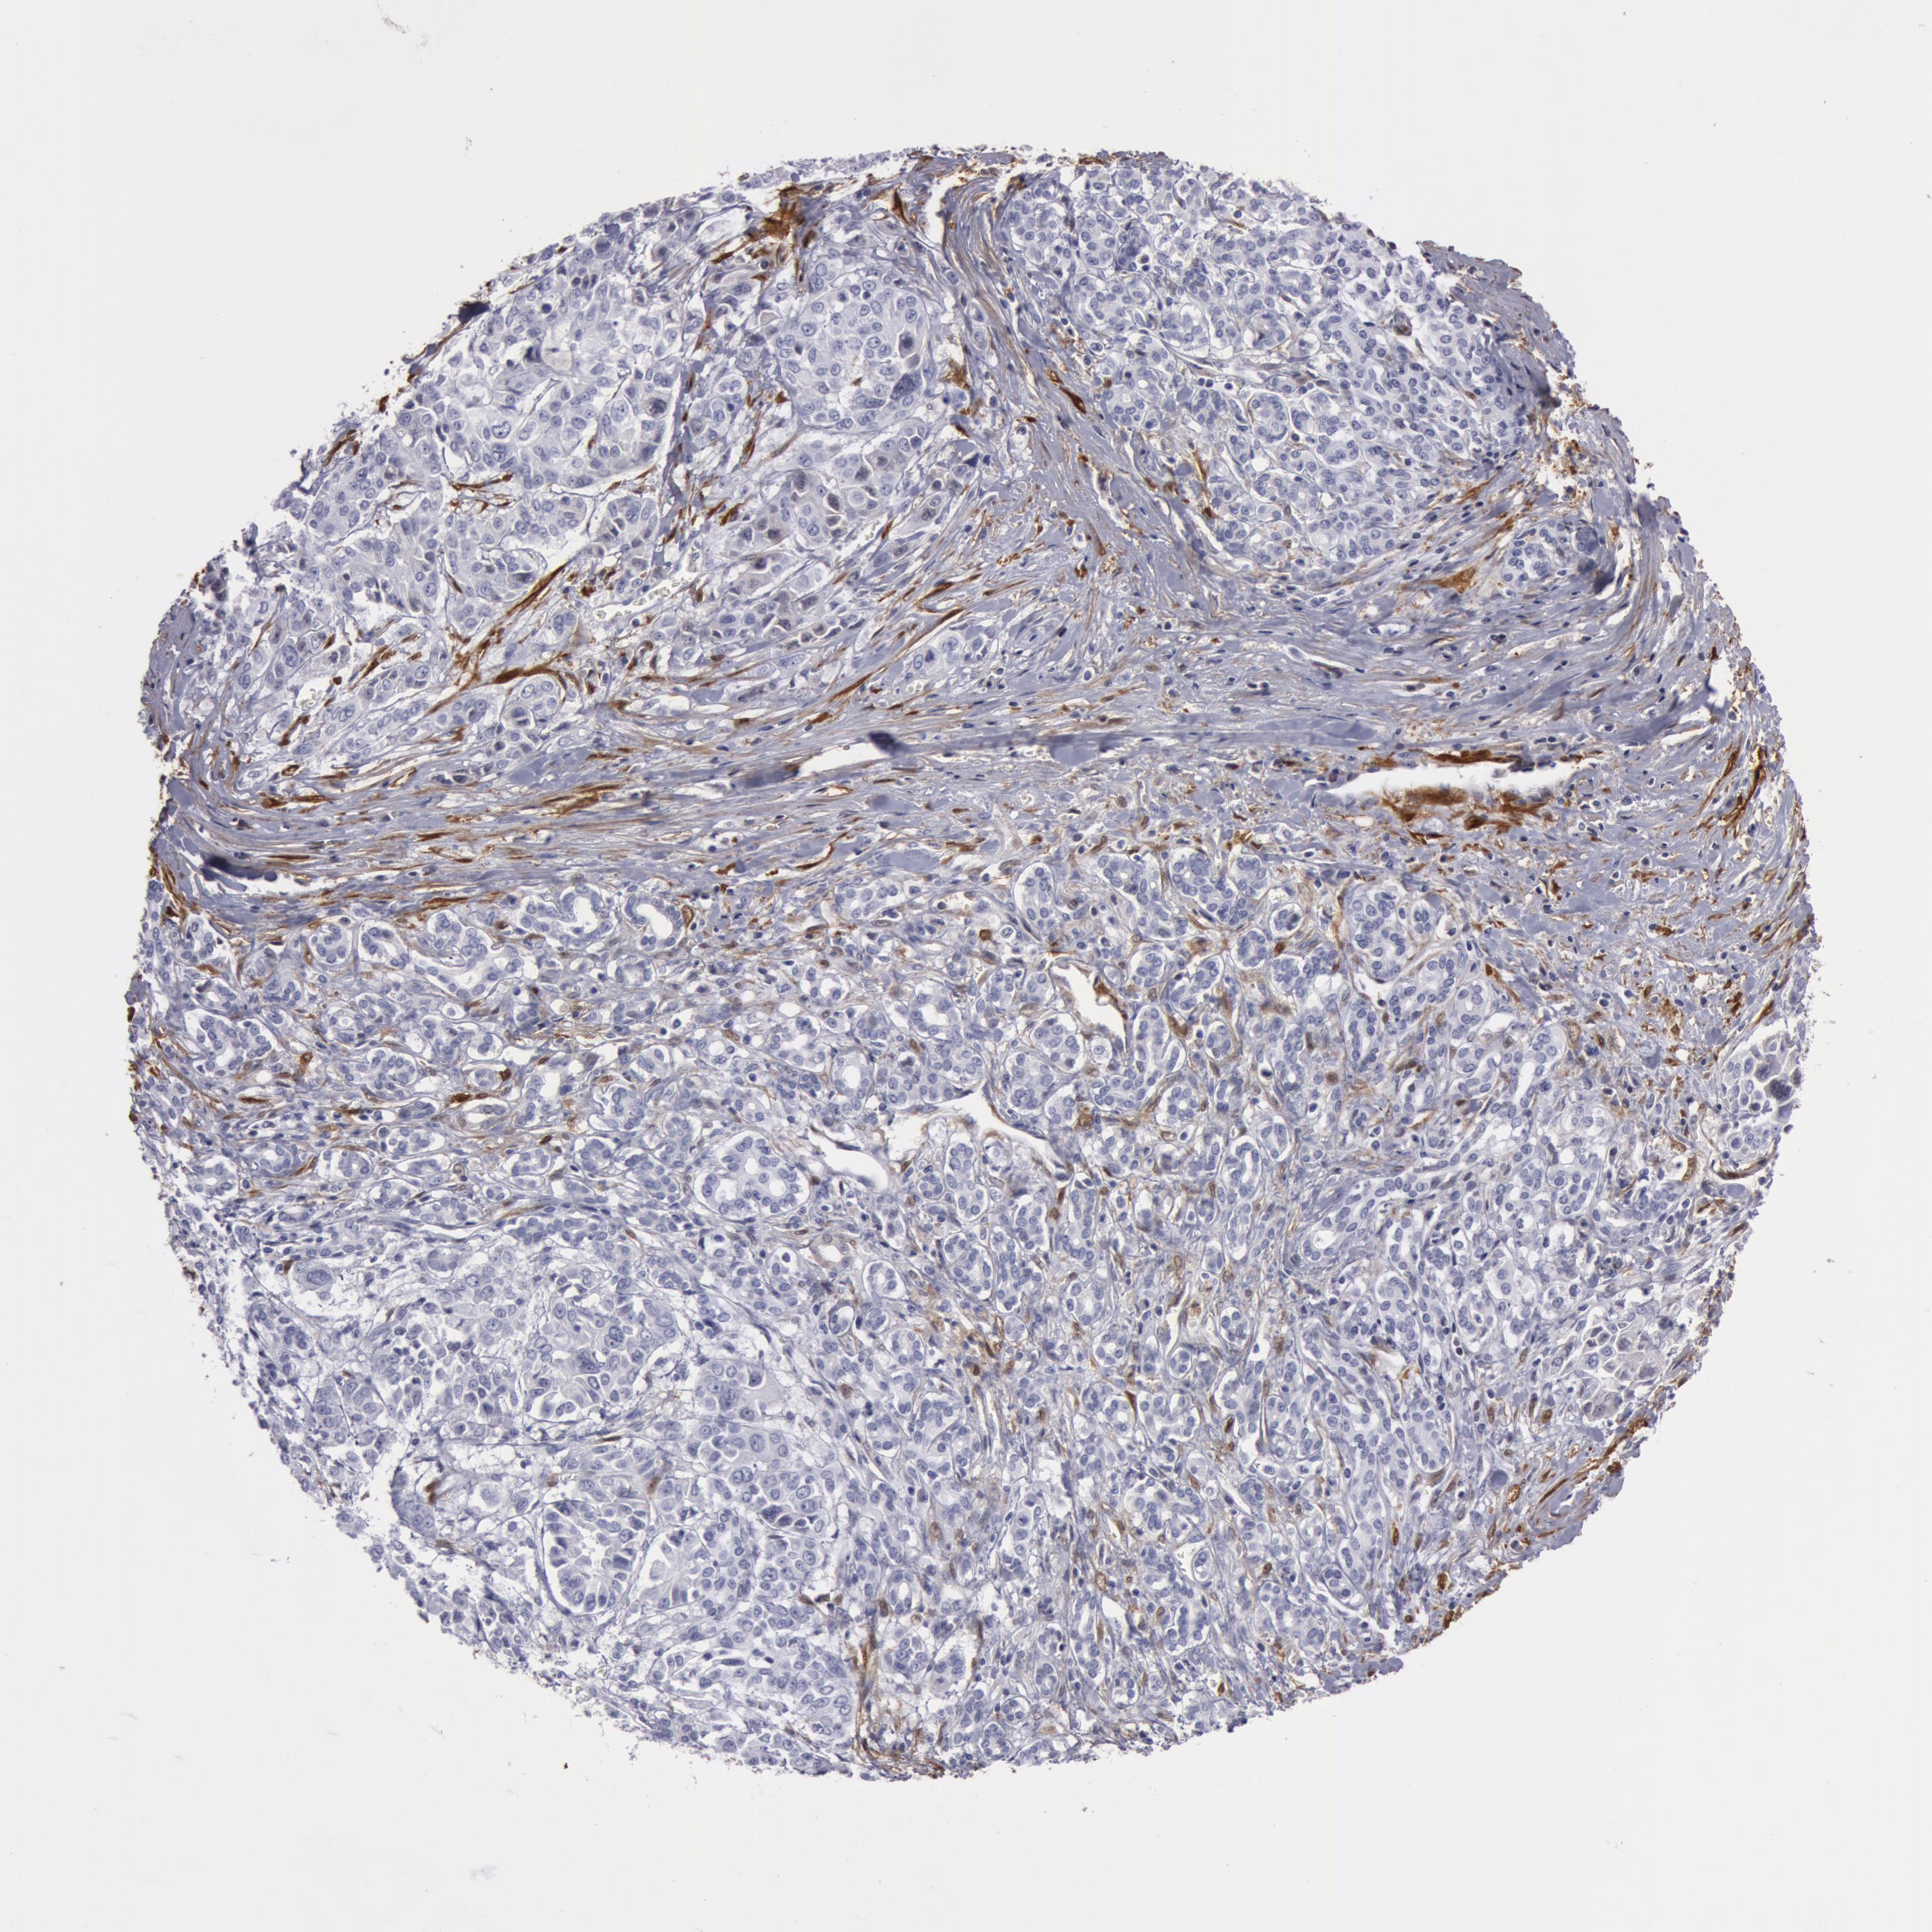

PANCREATIC CANCER - Protein expressioni

A mouse-over function shows sample information and annotation data. Click on an image to view it in a full screen mode. Samples can be filtered based on level of antibody staining by selecting one or several of the following categories: high, medium, low and not detected. The assay and annotation is described here.

Note that samples used for immunohistochemistry by the Human Protein Atlas do not correspond to samples in the TCGA dataset.

Antibody stainingi

Antibody staining in the annotated cell types in the current human tissue is reported as not detected, low, medium, or high, based on conventional immunohistochemistry profiling in selected tissues. This score is based on the combination of the staining intensity and fraction of stained cells.

Each image is clickable and will lead to virtual microscopy that enables deeper exploration of all samples and also displays staining intensity scores, fraction scores and subcellular localization as well as patient and tissue information for each sample.

Antibody HPA019467

Antibody HPA061657

Antibody CAB001447

Staining

High

Medium

Low

Not detected

Intensity

Strong

Moderate

Weak

Negative

Quantity

>75%

75%-25%

<25%

None

Location

Nuclear

Cytoplasmic/membranous

Cytoplasmic/membranous,nuclear

Adenocarcinoma, NOS